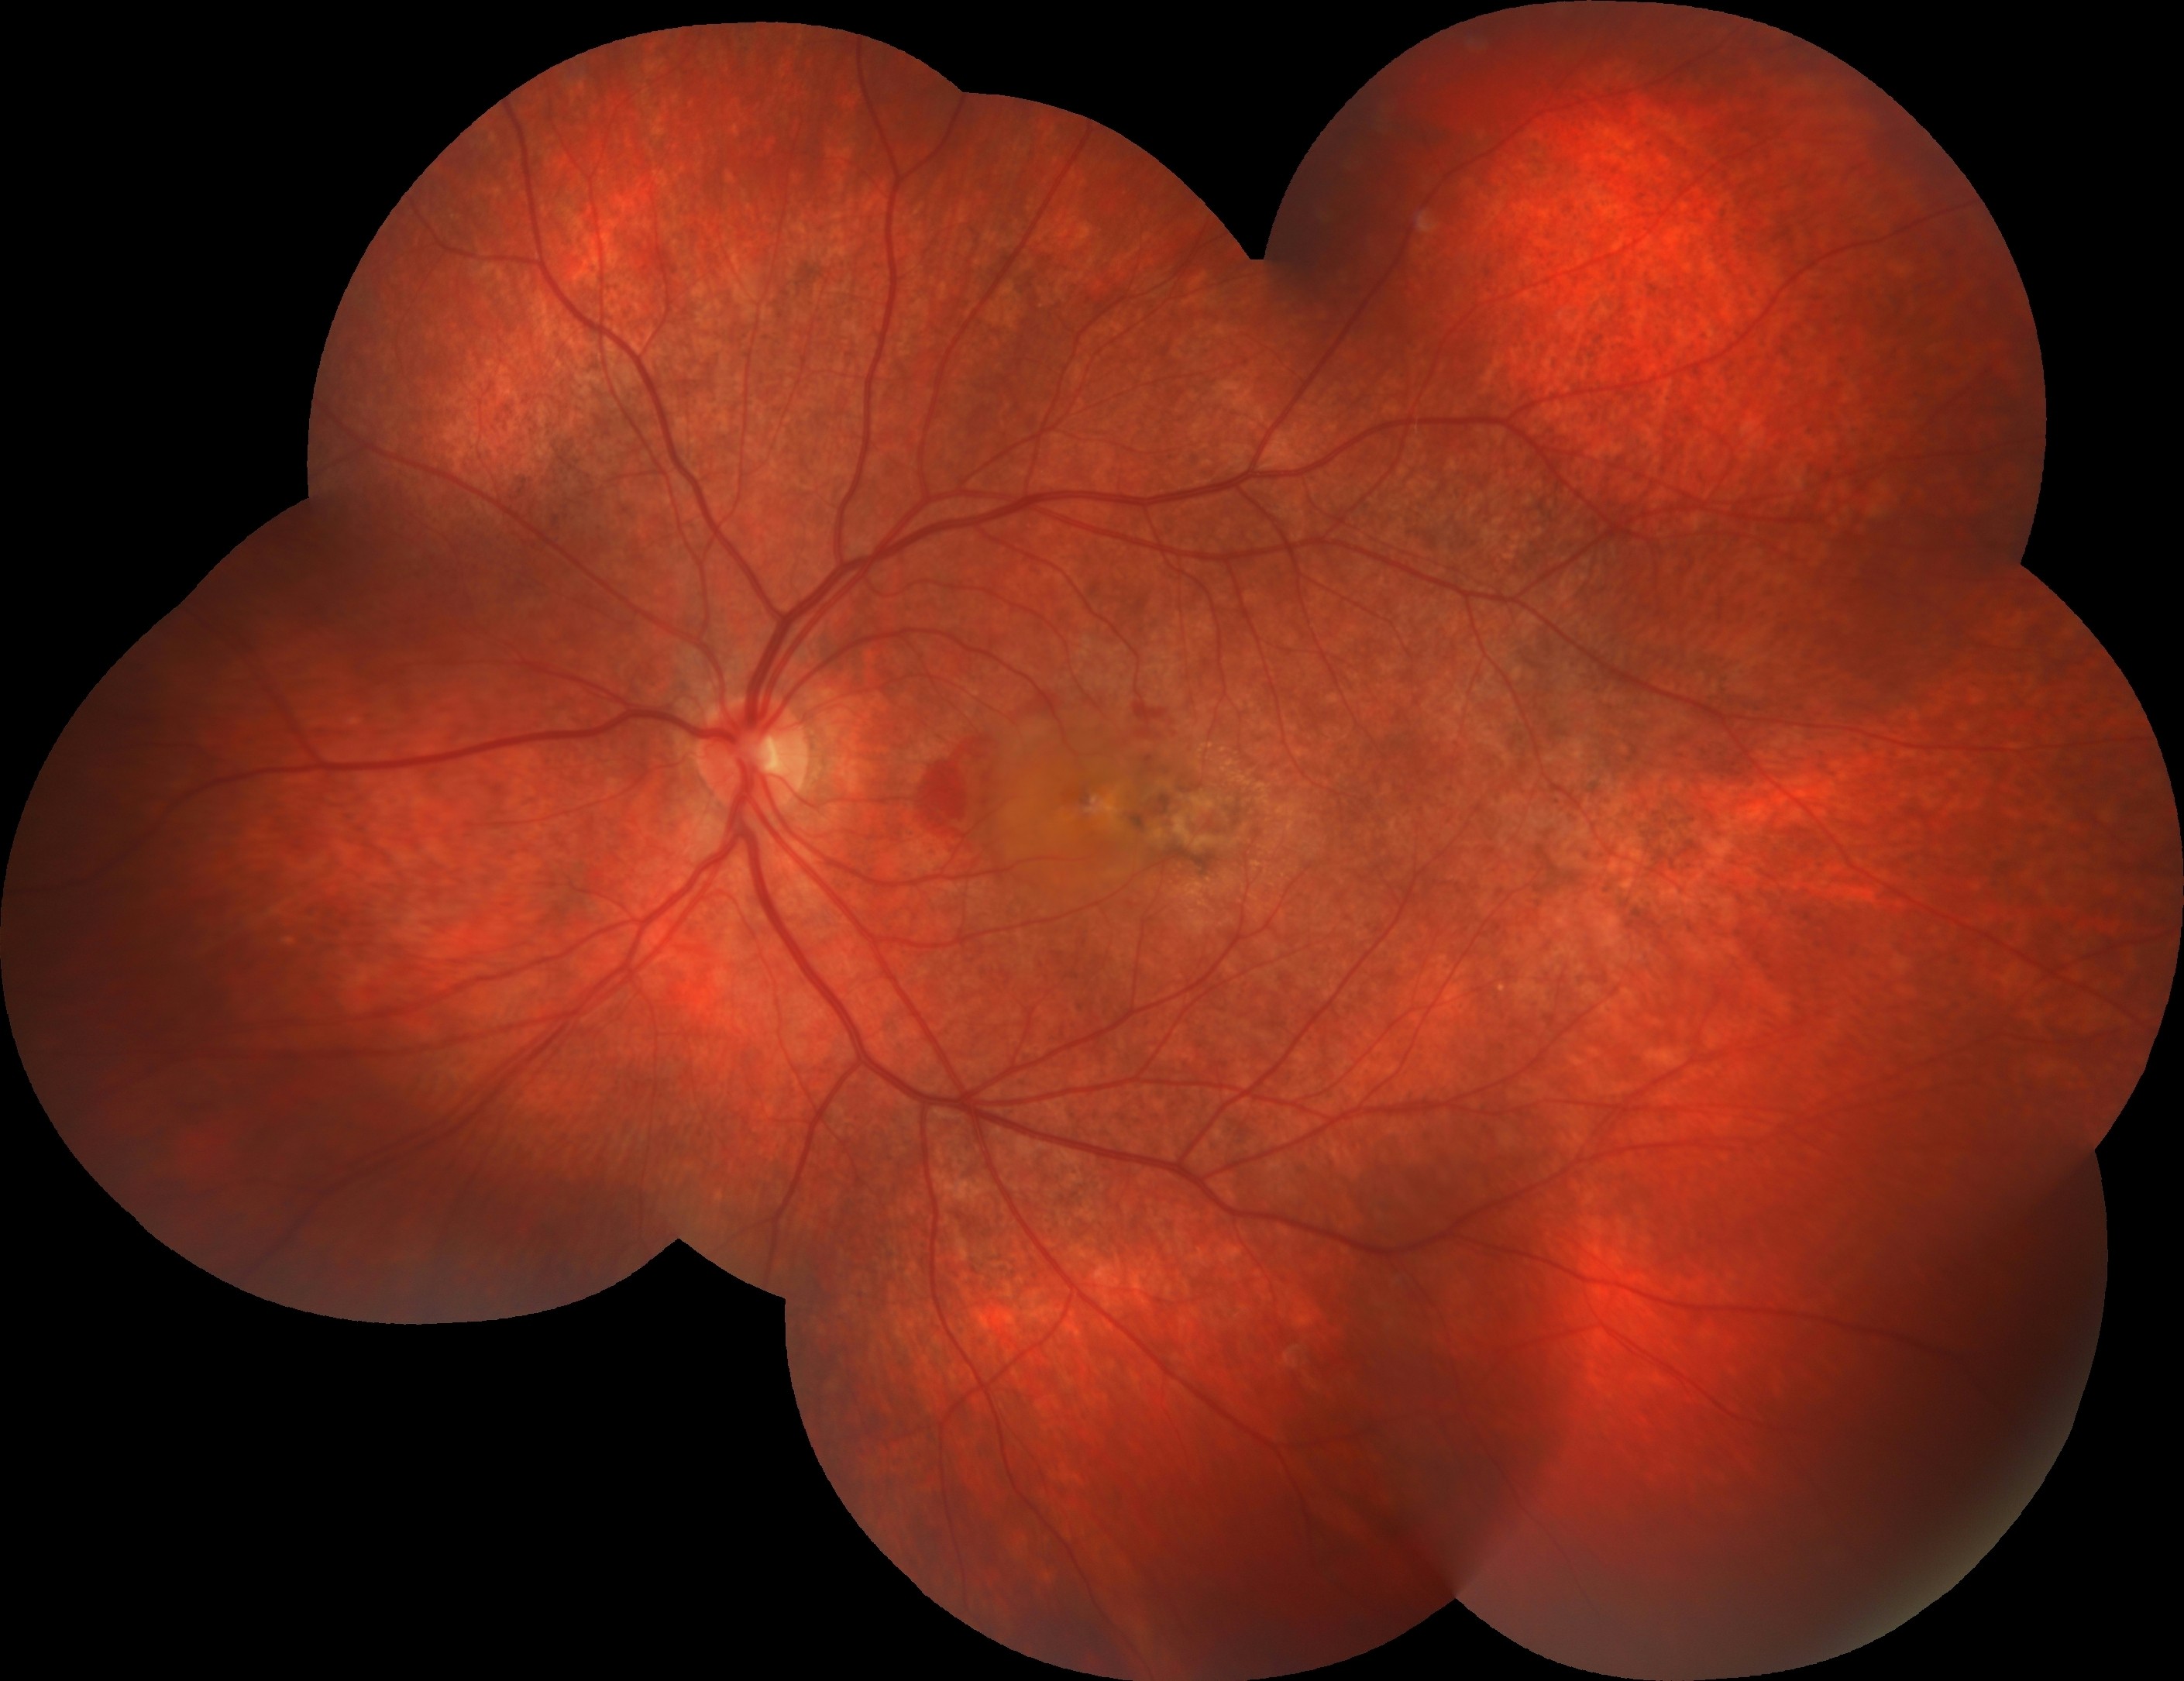

On ocular examination, the BCVA was 20/20 in the right eye and 20/400 in the left eye. IOPs were within normal limits in both eyes and anterior segment examinations were unremarkable. Dilated fundus examination of the right eye revealed a normal optic disk with a classical rubella retinopathy findings — a classic salt-and-pepper appearance of the retina that is due to the distribution of areas of increased and decreased pigmentation. In the left eye, in addition to classical rubella retinopathy findings appearance, a whitish subretinal lesion with retinal hemorrhages in the macula was detected. Mottling of the RPE was also evident in both eyes.

Fundus fluorescein angiography illustrated a pattern of diffuse spotty fluorescence because of the defective RPE without any leakage or staining in the right eye. On the left eye, in addition to diffuse spotty fluorescence, an active subfoveal CNV lesion, that hyperfluoresces in the early phases of the FFA, maintains well-demarcated borders, and leaks, was detected.

Fundus autofluorescence highlighted the fundus abnormalities patchy auto-fluorescence with a stippled hypo-fluorescence in both eyes, and also an hypo-autoflorescence area corresponding to the area of choroidal neovascularization in the left eye.